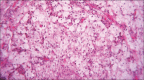

'Hibernoma' is a neoplasm that arises from vestiges of fetal brown fat, and its occurrence in oral cavity is extremely rare. Its most common locations include thighs, the inter-scapular region, and the cervical region. In the present case, a 37-year-old male patient reported to our department with a localized swelling on his lower left labial mucosa along with multiple cutaneous well-defined swellings on his right arm and abdominal region. Incisional biopsy was carried out. Histopathological examination revealed sheets of multi-vacuolated eosinophilic cells with the granular cytoplasm interspersed with fat cells suggestive of oral hibernoma. These are rare lesions and could be often a missed-out diagnosis. Therefore, it is imperative to consider oral hibernoma among the commonly considered differential diagnosis of oral mucosal swellings.